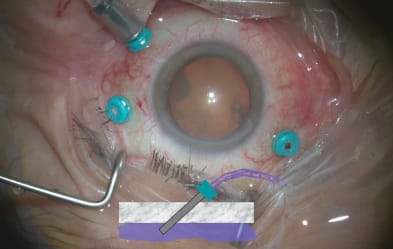

To achieve this, the surgeon should displace the conjunctiva before inserting the trocar. In addition, to make the chord length in the sclera as long as possible, I like to flatten the sclera with a broad stabilizing device on insertion of the trocar (Figures 1 and 2). This can be done with a cotton swab or with inserters. Finally, make the angle as oblique as possible to the sclera. The result is a wound that is not even visible, compared to the obvious wound gap and leakage found with straight incisions.

Figures 1 (above) and 2 (below). Flattening the sclera with a broad stabilizing device on insertion of the trocar can help in the lengthening of the wound.